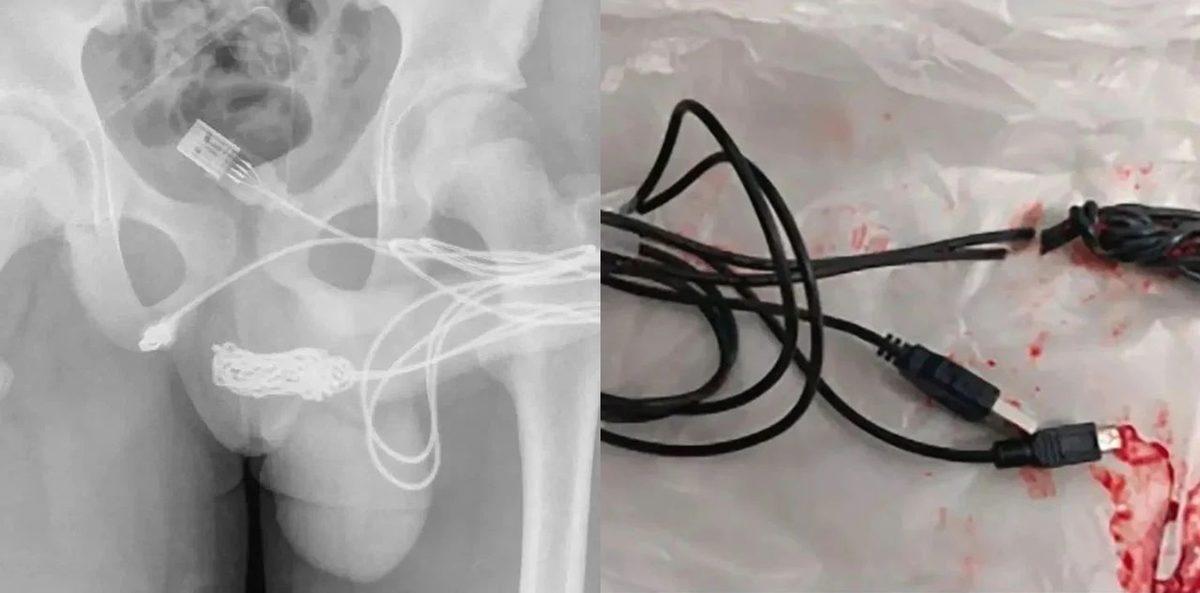

- Penis boyunu, üretrasına USB kablosu takarak ölçmeye çalışan bir adam!